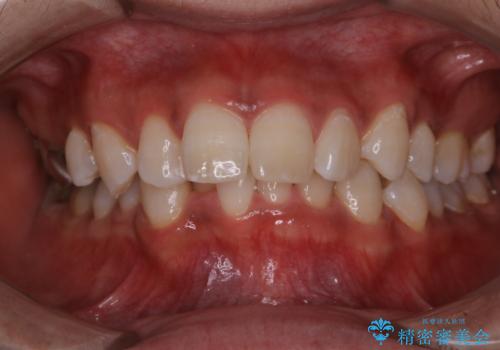

- 結婚式前にできる限りで白く、綺麗な歯にして欲しいとのことで来院されました。歯科は5.6年ぶりとのことでした。

PMTC60分コース(¥11000)とオフィスホワイトニング・エクセレントコース(¥29700)を行いました。

- ¥47000費用は治療当時の料金となります